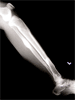

Post

Op

Treated with closed reduction, ligamentotaxis and ring fixator.Fibula brought to length by IM rod

Progress

Good healing of fracture(s) and fixator removed three months later

Excellent limb alignment and good knee/ankle motion